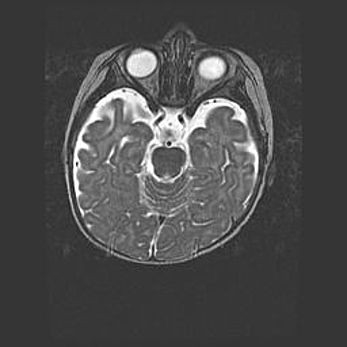

Мальформация Денди-Уокера. Киста задней черепной ямки.

Агенезия мозолистого тела.

Возраст: 2,5 месяца

Вес: 2420 г

Пол: женский

Окружность головы: 37 см

Срок гестации: 32 недели

Мальформация Денди—Уокера — редкий вид патологии ЦНС, представляющий собой врожденный порок развития каудального отдела ствола и червя мозжечка, ведущий к неполному раскрытию срединной (Мажанди) и латеральных (Лушка) апертур IV желудочка мозга. Для этогно синдрома характерна триада симптомов: гипотрофия червя мозжечка и/или полушарий мозжечка, кисты задней черепной ямки, гидроцефалия различной степени. В 70% случаев порок сочетается и с другими аномалиями головного мозга, в частности с агенезией мозолистого тела.